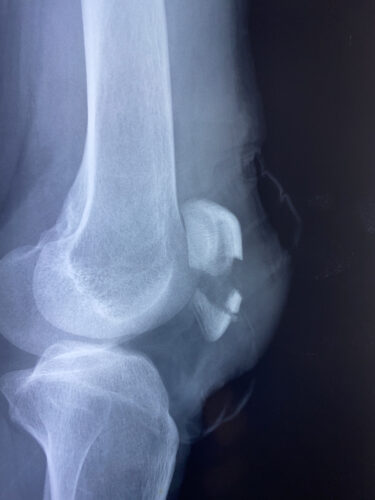

肘関節前方脱臼の1症例について